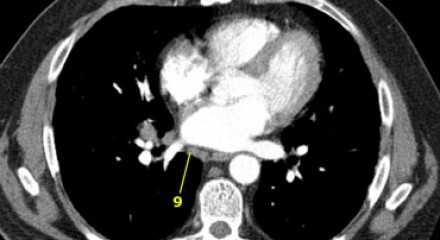

9. лимфатические узлы легочной связки

Данные лимфатические узлы лежат в пределах легочной связки, в том числе и по ходу нижней легочной вены. Легочная связка представлена дупликатурой медиастинальной плевры охватывающей корень легкого.

10. лимфатические узлы корня легкого

Лимфатические узлы корня расположены проксимальнее долевых узлов, но дистальнее медиастинальной дупликатуры и узлов промежуточного бронха справа.

Все лимфатические узлы 10-14 групп являются N1 узлами, так как они находятся вне средостения.